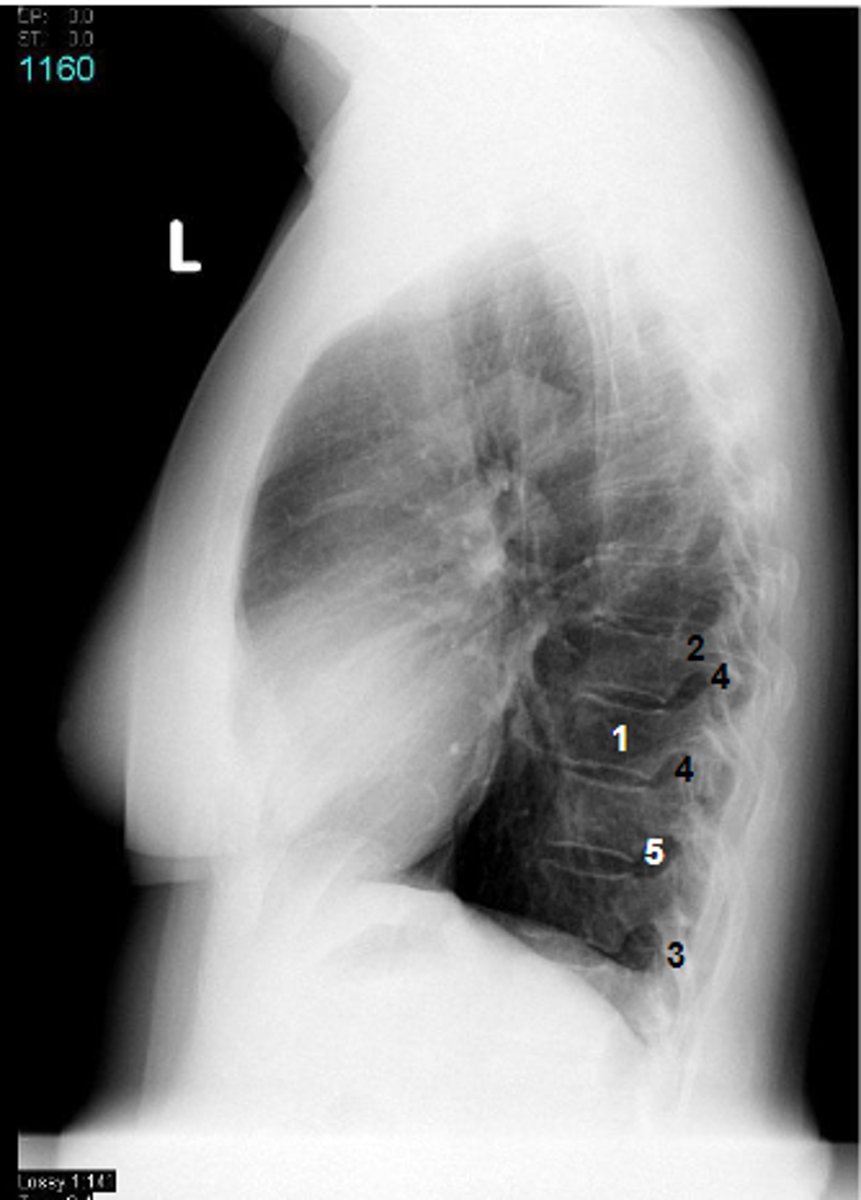

1

at what number is the sternum

2

at what number is the vertebral body

3

at what number is the vertebral canal/ spinal cord

4

at what number is the transverse process of vertebra

5

at what number is the rib

6

at what number is the spine of scapula

7

at what number is the trachea

8

at what number is the esophagus

9

at what number is the arch of aorta

10

at what number is the left subclavian artery

11

at what number is the common carotid artery

12

at what number is the brachiocephalic trunk

13

at what number is the superior vena cava

14

at what number is pectoralis major

15

at what number are Cooper's ligaments

16

at what number is the retromammary space

17

at what number is trapezius